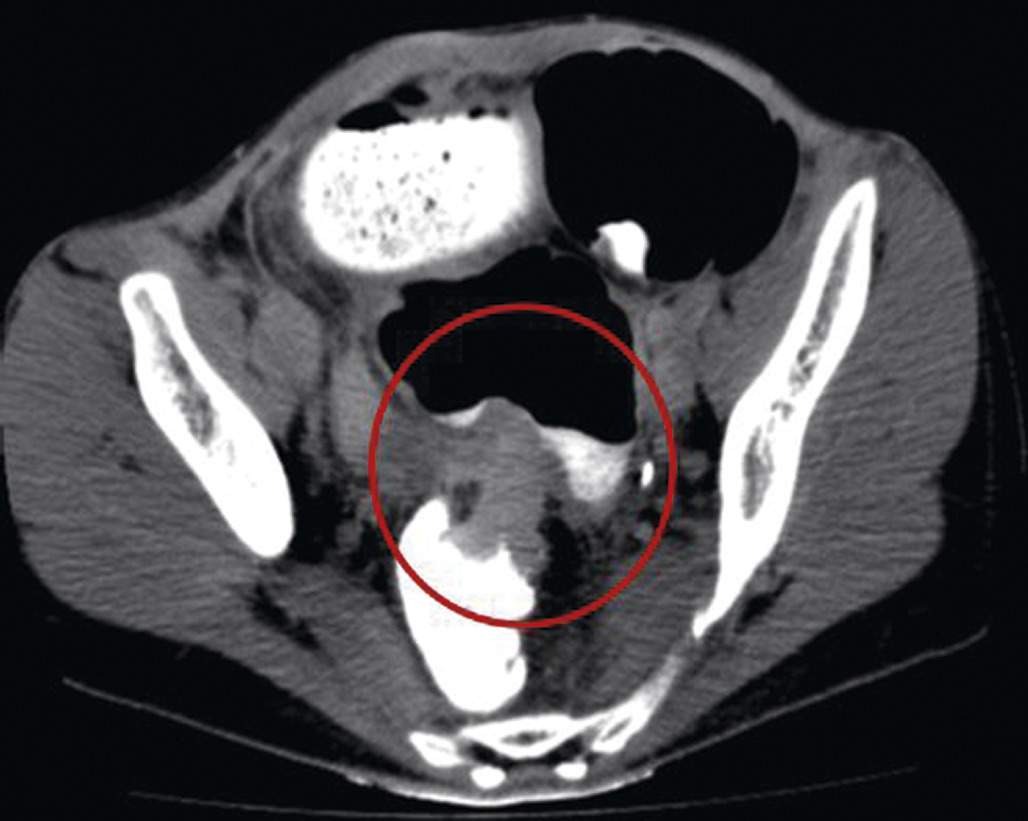

Les signes tomodensitométriques décelés sur le site de torsion sont classiquement (fig. 1 et 2) :

• anses dilatées, en forme de « U » ou de « C », à distribution radiaire ;

• présence de deux anses adjacentes collabées de forme ronde, ovale, triangulaire au niveau du site d’obstruction ;

• whirl sign, ou signe du tourbillon, qui correspond à l'enroulement des vaisseaux mésentériques et des mésos qui convergent vers le point de torsion mésentérique (fig. 1) ;

• le signe du bec, qui correspond à la visualisation, en coupe longitudinale, d’un aspect en pointe effilée reflétant à la diminution progressive du calibre intestinal jusqu'au niveau de l’obstruction (fig. 2).

Le signe des matières est fortement évocateur d’occlusion mécanique du grêle par bride, hernie ou tumeur.